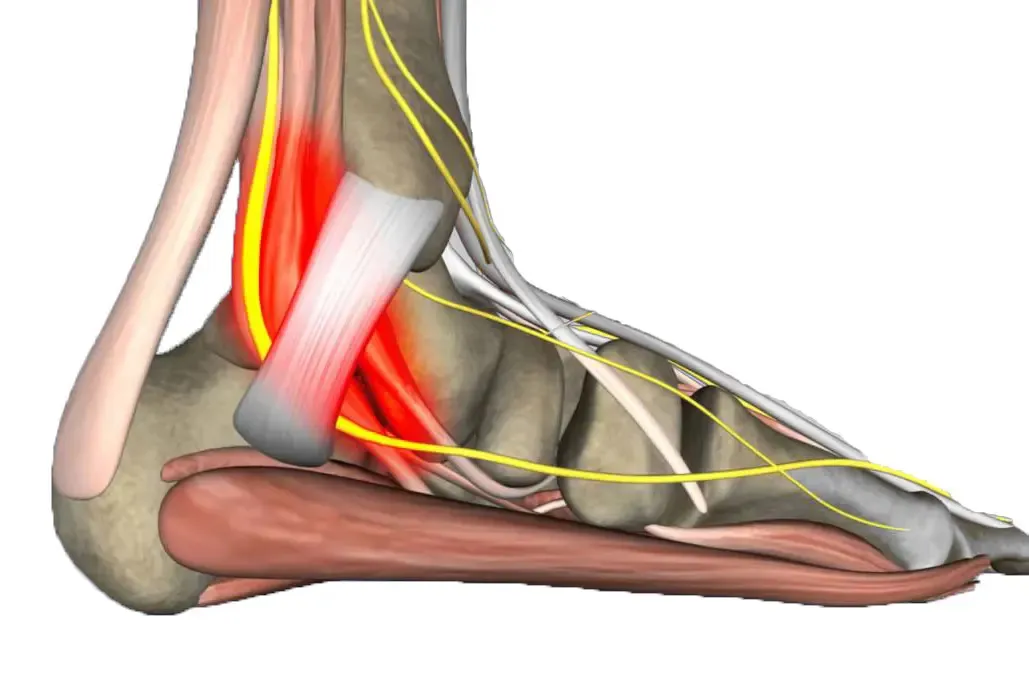

El dolor estaba localizado en la bursa retrocalcánea, una pequeña bolsa llena de líquido que actúa como amortiguador entre el tendón de Aquiles y el hueso calcáneo. Y el tendón de Aquiles también estaba sensible a la palpación.

Las radiografías muestran huesos, pero no pueden ver tejidos blandos como bursas o tendones. Por eso la ecografía podológica es fundamental en estos casos.

Al colocar el transductor ecográfico en la parte posterior del talón de María, la imagen fue clarificadora:

- Bursa retrocalcánea claramente engrosada con líquido en su interior (señal inequívoca de inflamación)

- Tendinosis leve del tendón de Aquiles distal con pérdida del patrón fibrilar normal

- El espolón calcáneo visible: presente, sí, pero sin signos inflamatorios alrededor, como un espectador silencioso

“¿Ve esta zona oscura, María? Esto es líquido inflamatorio en su bursa. Y aquí, el tendón de Aquiles muestra signos de sufrimiento. El espolón está ahí, pero no es el problema”.

Todo empezaba a tener sentido. Las zapatillas nuevas de María tenían un contrafuerte rígido (la parte trasera del zapato) que rozaba constantemente contra la bursa retrocalcánea. Además, el drop elevado (diferencia de altura entre talón y puntera) modificaba su biomecánica, aumentando la tensión sobre el tendón de Aquiles.

El resultado: una bursitis retrocalcánea con tendinopatía aquilea distal. No fasciopatía plantar. No “dolor de espolón”. Un diagnóstico completamente diferente que requería un tratamiento completamente diferente.

- Deformidad de Haglund leve (prominencia ósea posterior) que hacía más vulnerable la bursa